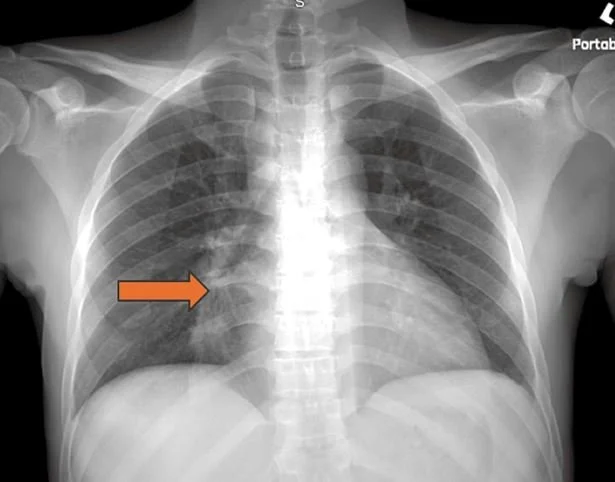

histo can mimic tuberculosis or sarcoid with granulomas and lymphadenopathy